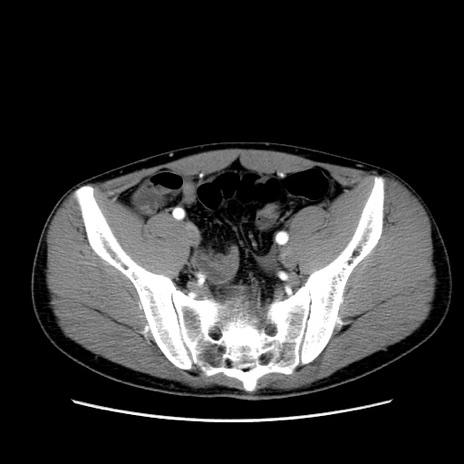

症例36(横断像)

【症例】20歳代 男性

【主訴】心窩部痛

【現病歴】今朝より上腹部痛あり。一旦軽快していたが再度出現したため救急要請。昨日夕に白身の魚を含む刺身を食べた。

【身体所見】BP 136/89mmHg、HR 74/min、BT 37.0℃、腹部:膨満、軟、心窩部に圧痛あり。反跳痛なし、筋性防御なし、腸雑音やや亢進あり。

【データ】WBC 17700、CRP 0.48